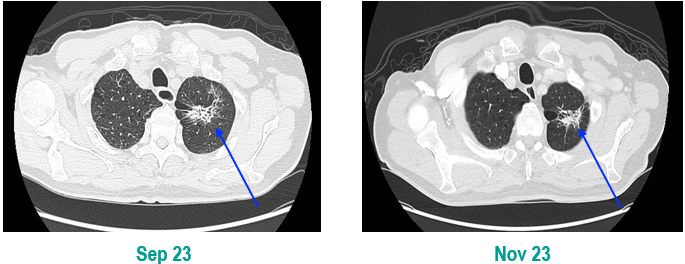

PET-CT(2023年9月):右下肺叶发现6.9×6.7×6.6cm的FDG高摄取肿块,伴右侧第7、8肋骨侵犯可疑,右肺门淋巴结肿大,双肺上叶多发结节,考虑腺癌谱系疾病。

CT及PET-CT随访(2023年11月、2024年1月):评估新辅助治疗效果,右下肺叶肿块缩小,右肺门淋巴结代谢活性消失,右肺上叶结节稳定但代谢活性降低,左肺上叶及双侧磨玻璃样病变稳定。